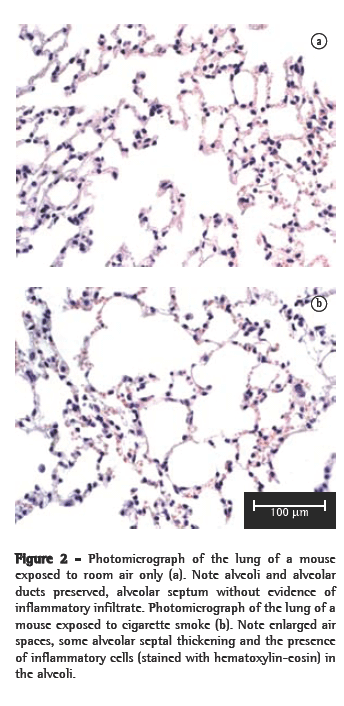

However, no significant differences in the number of neutrophils were observed. In the histological analysis, samples from the control group animals (exposed to room air only) presented preserved alveoli with thin alveolar septa and a minimal number of alveolar macrophages (Figure 2a). The CS10 and CS20 group samples presented a histological pattern with progressive alterations of breakage of alveolar septa with a greater number of alveolar macrophages. The CS30 group samples presented an initial pattern of alterations in the lung architecture principally with enlargements of the air spaces corresponding to the alveolar duct and alveoli. The CS60 group samples presented a typical pattern of murine emphysema, with alveolar enlargement and areas of initial fibrosis (Figure 2b).